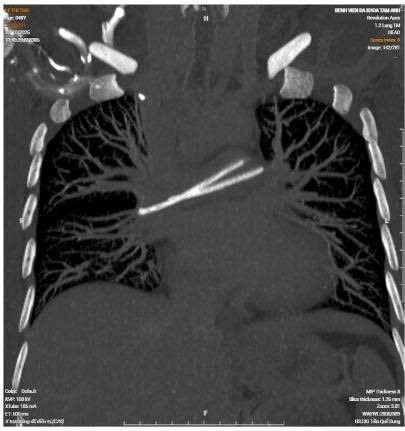

Hình ảnh CT ghi nhận dị vật bên động mạch phổi, CT - Ảnh BVCC

Bác sĩ ghi nhận catheter đã bị đứt, một phần còn tại vị trí dưới xương đòn phải, phần đầu ống truyền còn lại đã di chuyển về tim và nằm trong động mạch phổi. Bệnh nhân được chỉ định rạch lấy phần catheter còn lại dưới da, lấy phần catheter ra ngoài và được tư vấn đến Bệnh viện Quân y 175 để xử trí chuyên sâu phần trong tim.